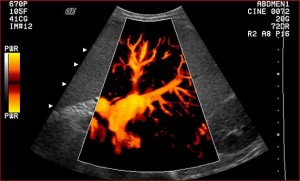

Ultrasound is one of the most essential diagnostic tools in equine orthopedics and equine sports medicine, allowing us to obtain detailed and real-time images of soft tissues, joints and internal organs. As an equine orthopedic veterinarian (PhD) based in Belgium, I use high-resolution ultrasound to diagnose injuries early, monitor healing, and support decision-making for sport horses competing across Europe.

Using ultrasound, we can precisely identify fiber disruption, inflammation, adhesions, and early degenerative changes—key information to design a personalized rehabilitation program and prevent reinjury.

Beyond orthopedics, ultrasound is also invaluable for: